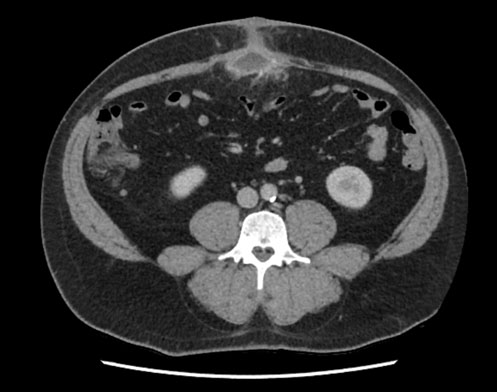

An 85-year-old female patient presented to the emergency unit with a 3-day history of abdominal pain, vomiting, and constipation. She had a medical history of Alzheimer’s disease, hypertension and a midline laparotomy for perforated ulcer 30 years ago. Physical examination revealed diffuse abdominal tenderness with an incarcerated sub-umbilical bulge on the midline incision. Abdominal computed tomography scan confirmed the presence of an incarcerated incisional hernia containing a portion of the small bowel (Figure 1). The patient undergone emergency laparotomy. Small bowel resection followed by anastomosis was performed (Figure 2) and the abdominal wall was repaired by herniorrhaphy without mesh. Histopathologic analysis of the specimen showed a necrotic Meckel diverticulum without malignancy. Postoperative course was uneventful and the patient presented no hernia recurrence at the 6-month follow-up control.

Figure 1: Abdominal computed tomography, in axial (A) and sagittal plane (B), showing the incarcerated incisional hernia containing small bowel (arrows).